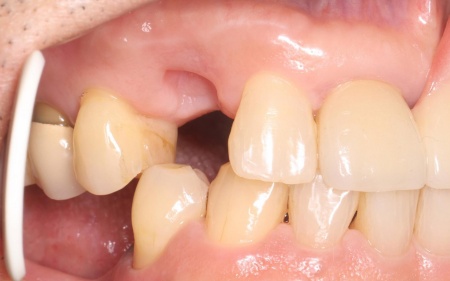

| 行ったご提案・治療内容 | 抜歯後に歯を補う方法には、欠損歯の両隣の歯を支えにして歯を補うブリッジ・インプラント・入れ歯の3つの治療法がありますが、患者様の場合、右上の犬歯の両隣の歯は治療されているためブリッジによる治療は困難です。 そこで、インプラントまたは入れ歯による治療を提案しました。 ・インプラント ・取り外し式の部分入れ歯 患者様は当初インプラントを希望されたものの、治療期間が長くなることから「まずは入れ歯で様子をみたい」とバルプラストによる治療を選択されました。 まず、感染の拡大を防ぐために右上犬歯の抜歯を行い、歯ぐきや骨が安定するまで一定期間経過を観察します。 |

治療中